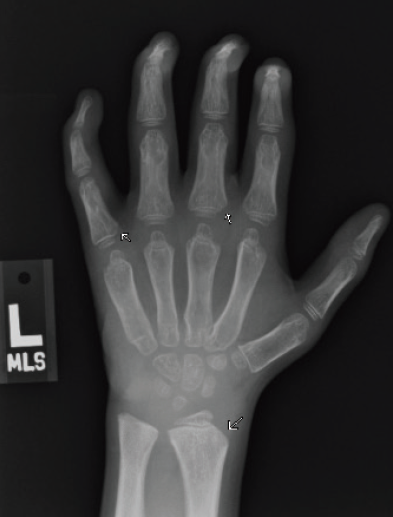

Figure 3A. Posteroanterior radiograph of the left hand.

Figure 3B. Posteroanterior radiograph of the right hand. Posteroanterior radiographs of both hands demonstrate fixed contractures of the distal interphalangeal joints, slightly “bullet-shaped” phalanges with osteopenia, broadening of the metacarpals, and dysplastic appearance of the distal radii.

There were multiple abnormalities noted in several of these images. The hips and pelvis were noted to have bilateral coxa valga, and the lateral aspects of both femoral heads were incompletely covered by the acetabulae. His sacroiliac joints were noted to be widened, and the lumbar spine demonstrated shortened height of the vertebral bodies. There was soft tissue swelling or redundancy at the bilateral wrists and decreased bone mineralization. Images of his elbows showed loss of skin folds at the bilateral anterior elbows consistent with soft tissue swelling, possibly related to chronic contractures. Views of his hand showed moderate fixed flexion of the bilateral DIP joints along with bilateral soft tissue swelling, enlargement, osteopenia and gross abnormalities (Figures 3A and 3B). The lumbar spine images showed vertebral body height loss as well as posterior vertebral body scalloping most pronounced at the lower lumbar spine. It was also noted that on the anteroposterior view there was demonstration of possible hepatomegaly. Overall, interpretation by pediatric radiology noted that the findings raised concern for a possible underlying genetic disorder.